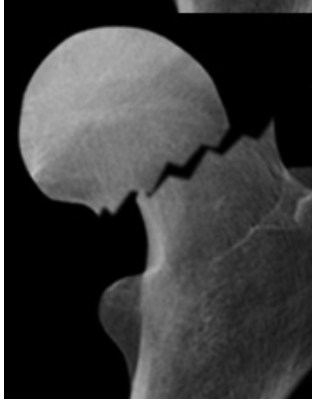

Which type of Garden classification is shown [1]

III - Complete - partially displaced

I - Incomplete or impacted bone injury with valgus angulation of the distal component

What type of Garden classification is this? [1]

IV - Complete - totally displaced

What classification of Garden fracture is this? [1]

Garden IV fracture

* Loss of Shenton’s line

* Complete fracture of the full diameter of the femoral neck

* Total displacement of the 2 fracture components